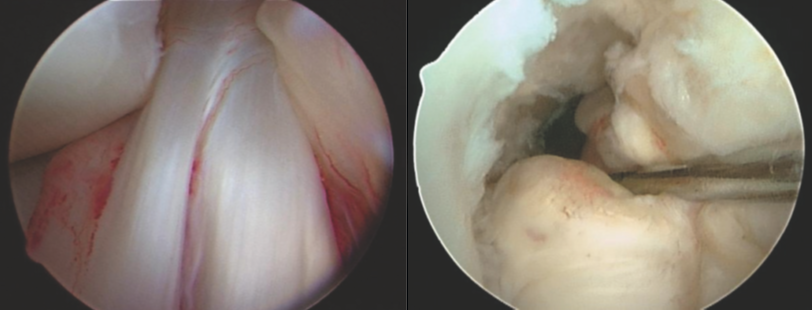

Los Meniscos

Son fibrocartílagos en forma de medialuna y tienen como funciones: Estabilizar la articulación de la rodilla, amortiguar, absorber carga y con esto protegen de daños a los cartílagos, nutren y lubrican además de estar implicados en la propiocepción de la rodilla.

Son avasculares en sus 2/3 partes lo que hace difícil su cicatrización espontánea y nos vemos en la necesidad de salvar al menisco haciendo un diagnóstico temprano y tratamiento artroscópico adecuado.